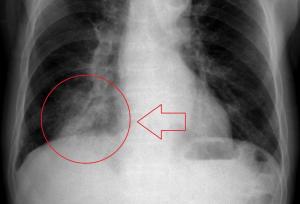

Getting back to the Zenker’s Diverticulum.  My swallowing/choking was not the worst situation I was dealing with.  That diverticulum is a pouch, and a pouch holds stuff.  In the throat, it can hold food, or, it can hold acid, as from reflux.  And with the food and air sharing the same entry point, air inhaled, carries the bacteria from the diverticulum, into the lung.  Complicate that with the lower left lobe of my lung “dead” from radiation damage, the fact that this pneumonia was in that particular part of my lung, I was going to die, perhaps within hours.  Blood levels show that I was septic for at least 48 hours.  I have done a separate post on this incident.